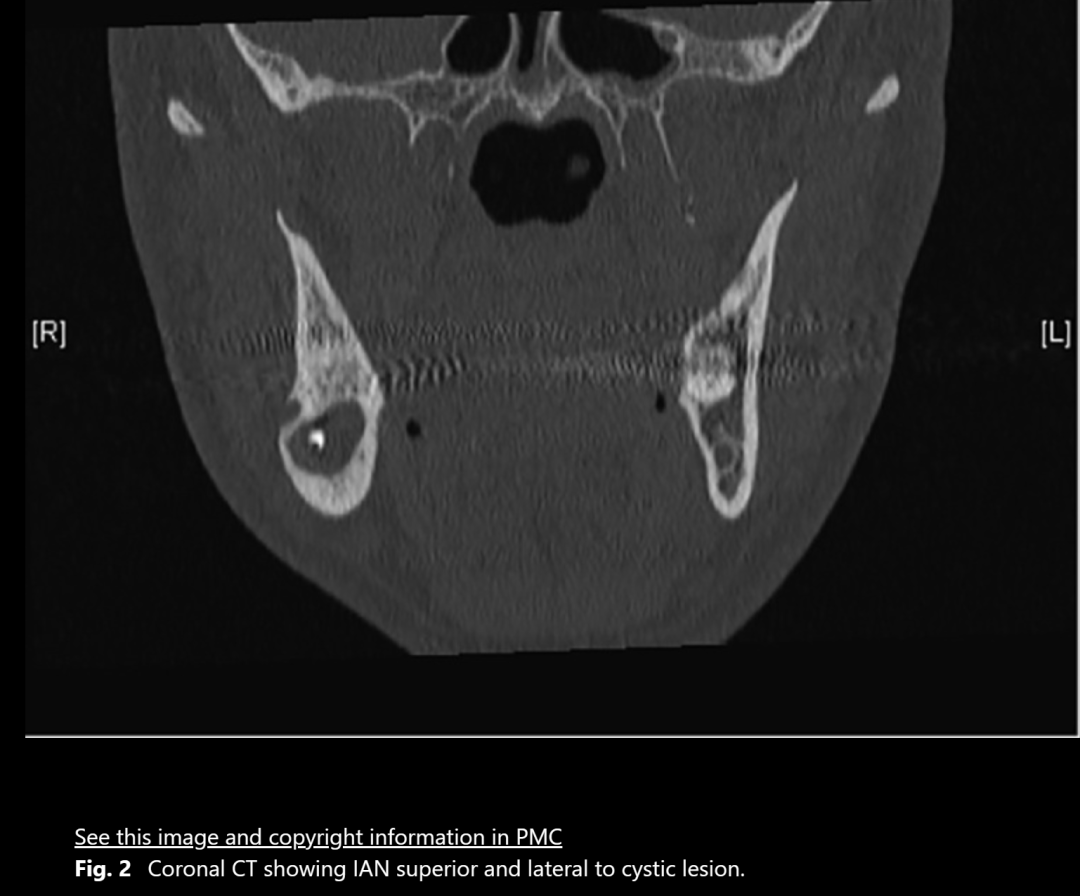

图2:冠状面看位于囊肿上方和颊侧(一般偏舌侧)

下牙槽神经被提起后,骨板上的凹槽显露出来。进一步对CT图像进行检查,确认下颌神经从颊侧骨板穿出,并且在神经与囊肿之间存在正常骨质,下颌神经在一个开放的通道内自由移动。

关于下牙槽神经的走向,已有众多解剖学和影像学研究。在大多数情况下,下颌神经位于阻生第三磨牙下方,且其与牙齿的位置关系通常在颊舌方向上变化。Maegawa等人发现,74%的下颌神经在下颌第三磨牙下方和舌侧运行。本案例中,下颌神经在第三磨牙上方和颊侧的位置非常罕见。我们认为这是第一个临床与放射学关联的外露下颌神经报告(图2、图3)。目前文献中尚无相关变异发生率的信息。

有观点认为我们的发现可能是囊肿造成的,而非解剖变异。然而,考虑到没有骨扩张或下颌轮廓变化,我们认为这种变异更可能是解剖性的。囊肿与神经之间存在完整的骨板进一步支持了这一假设。虽然已知牙源性囊肿可导致下颌神经管位移,但在18.1%的牙源性囊肿中,下颌神经的外露未被报告。因此,我们认为在此情况下看到的神经外露更可能是解剖变异,而非病理性结果。